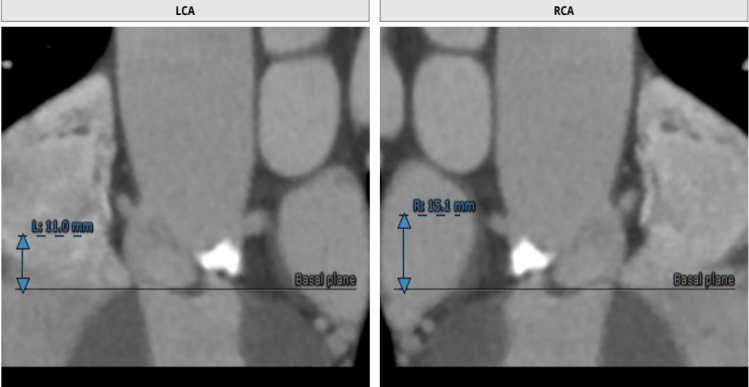

TYPE 0型主动脉瓣,瓣环径22mm,瓣上结构分析仅有左侧窦单瓣叶钙化,右侧窦瓣叶柔软无支撑。应用downsize策略(23mm瓣膜)不排除会出现瓣膜固定不稳,飞瓣或下滑可能。

左侧窦瓣叶钙化,左侧窦平且冠脉高度不足,右侧窦也不大,且预计瓣叶长度高于右冠高度,双侧冠脉均有遮挡风险。